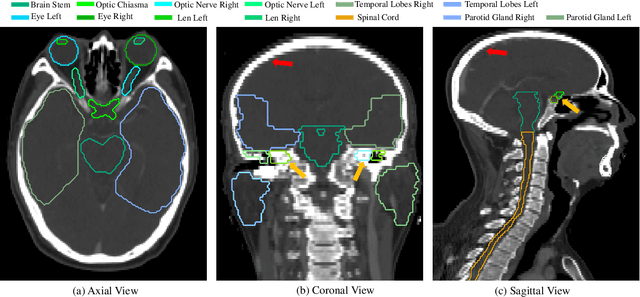

Abstract:Nasopharyngeal Carcinoma (NPC) is a leading form of Head-and-Neck (HAN) cancer in the Arctic, China, Southeast Asia, and the Middle East/North Africa. Accurate segmentation of Organs-at-Risk (OAR) from Computed Tomography (CT) images with uncertainty information is critical for effective planning of radiation therapy for NPC treatment. Despite the stateof-the-art performance achieved by Convolutional Neural Networks (CNNs) for automatic segmentation of OARs, existing methods do not provide uncertainty estimation of the segmentation results for treatment planning, and their accuracy is still limited by several factors, including the low contrast of soft tissues in CT, highly imbalanced sizes of OARs and large inter-slice spacing. To address these problems, we propose a novel framework for accurate OAR segmentation with reliable uncertainty estimation. First, we propose a Segmental Linear Function (SLF) to transform the intensity of CT images to make multiple organs more distinguishable than existing methods based on a simple window width/level that often gives a better visibility of one organ while hiding the others. Second, to deal with the large inter-slice spacing, we introduce a novel 2.5D network (named as 3D-SepNet) specially designed for dealing with clinic HAN CT scans with anisotropic spacing. Thirdly, existing hardness-aware loss function often deal with class-level hardness, but our proposed attention to hard voxels (ATH) uses a voxel-level hardness strategy, which is more suitable to dealing with some hard regions despite that its corresponding class may be easy. Our code is now available at https://github.com/HiLab-git/SepNet.